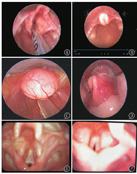

60例咽喉部特殊结构异常患儿中,鼻塞/张口呼吸7例(11.67%),憋气39例(65.00%),喉鸣44例(73.33%),呛奶和声嘶各25例(各占41.67%),吞咽困难18例(30.00%)。19例(31.67%)患儿并多种畸形及合并症,如先天性心脏病、VCTERL综合征、腭裂、马蹄内翻足、食管裂孔疝等。47例(78.33%)并肺炎。除依据临床表现,辅助检查是确诊的重要手段(图1、图2),60例患儿中依靠鼻咽喉镜确诊者52例(86.67%),依赖增强CT确诊者10例(16.67%)。73例喉软化患儿均依靠鼻咽喉镜确诊。

本研究显示,60例(45.12%)特殊咽喉结构异常患儿中咽喉部肿物26例,以舌根囊肿最多[12例(9.02%)],其他还有咽部肿物4例(3.00%),会厌囊肿3例(2.25%),喉囊肿2例(1.50%),喉部肿物(性质不明)、喉部前肠囊肿、实性成熟性畸胎瘤、喉部神经胶质瘤、声门下囊肿各1例(各占0.75%),部分患儿需病理结果辅助诊断。囊肿的通常表现为喂养困难、生长迟滞、喘鸣、呼吸时伴杂音、呼吸窘迫或哭声嘶哑,可伴喉软化。纤维喉镜可确诊。咽喉部囊肿易发生上呼吸道梗阻的急性表现,故需早期诊断和治疗。本研究中咽喉部囊肿的治疗以手术治疗为主,预后良好。